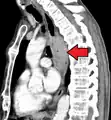

Although an occlusive tumor may be suspected on a barium swallow or barium meal, the diagnosis is best made with an examination using an endoscope. This involves the passing of a flexible tube with a light and camera down the esophagus and examining the wall, and is called an esophagogastroduodenoscopy. Biopsies taken of suspicious lesions are then examined histologically for signs of malignancy.

Additional testing is needed to assess how much the cancer has spread (see #Staging, below). Computed tomography (CT) of the chest, abdomen and pelvis can evaluate whether the cancer has spread to adjacent tissues or distant organs (especially liver and lymph nodes). The sensitivity of a CT scan is limited by its ability to detect masses (e.g. enlarged lymph nodes or involved organs) generally larger than 1 cm.[41][42] Positron emission tomography is also used to estimate the extent of the disease and is regarded as more precise than CT alone.[43] Esophageal endoscopic ultrasound can provide staging information regarding the level of tumor invasion, and possible spread to regional lymph nodes.

-

Endoscopic image of Barrett esophagus – a frequent precursor of esophageal adenocarcinoma -

Endoscopy and radial endoscopic ultrasound images of a submucosal tumor in the central portion of the esophagus -

Contrast CT scan showing an esophageal tumor (axial view)

Contrast CT scan showing an esophageal tumor (coronal view)